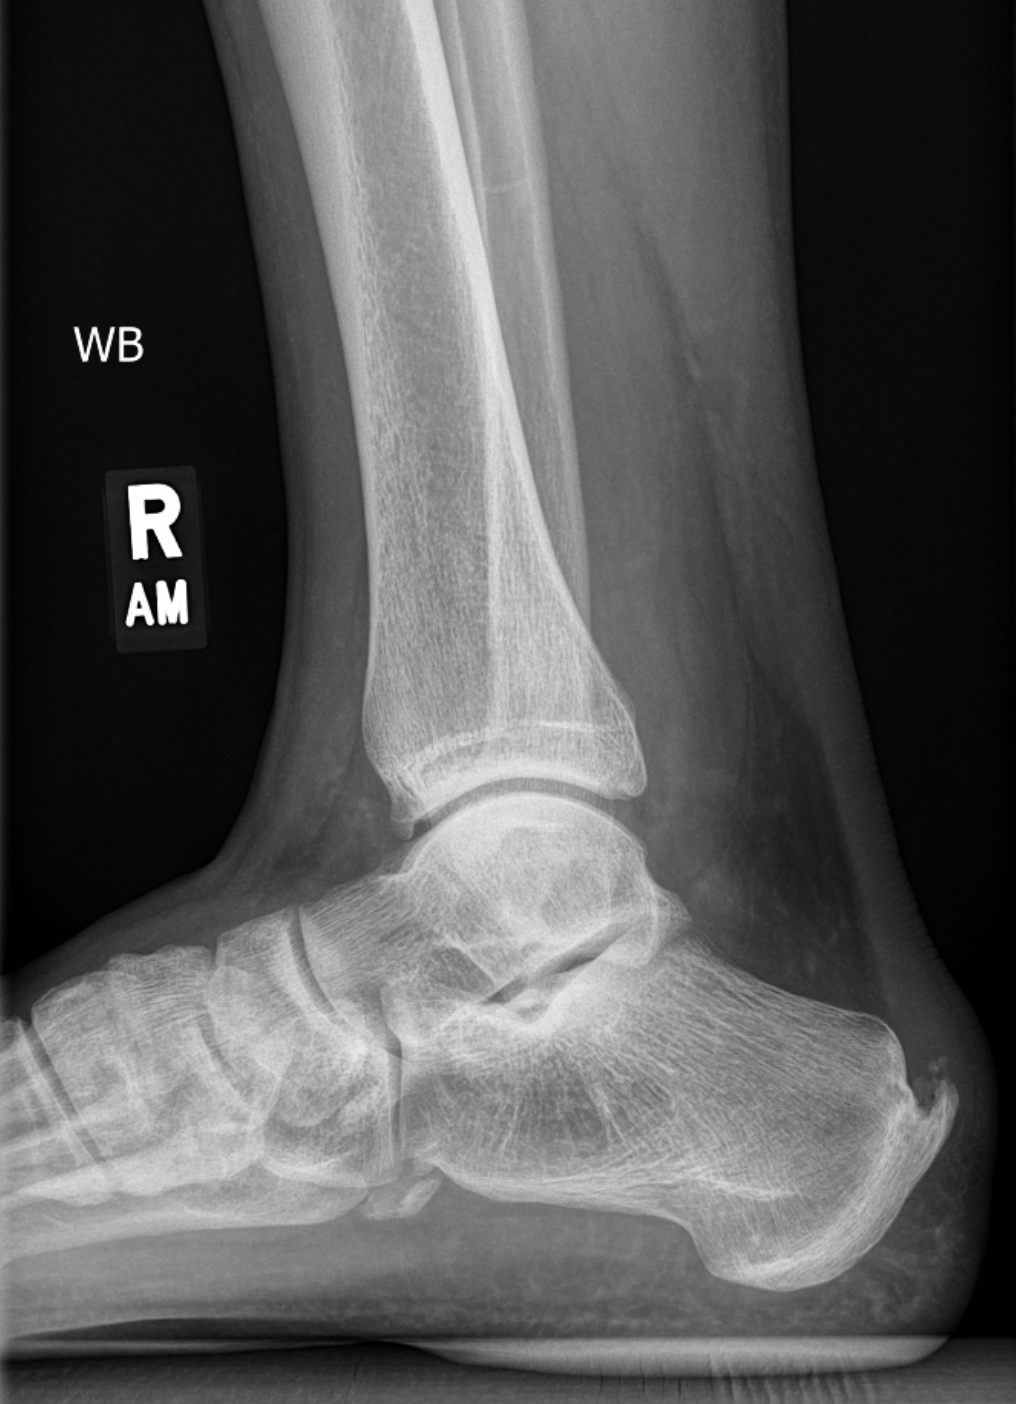

X-ray showing bone growth on the back of Jonathan’s heel

For well over a year, Professor Jonathan Peelle had a tender Achilles tendon. Physical therapy helped some, but couldn’t solve the problem, which was due to a bone growth on the back of his heal (a Haglund’s deformity). As long as the bone was rubbing the tendon, there would be pain. Jonathan’s surgeon recommended a repair which involved removing the tendon, getting rid of the bone, and then reattaching the tendon (video here). The recovery would require much reduced weight-bearing for a period of several weeks (using a scooter or crutches for at least 2 weeks). Remembering the above-mentioned study on limb disuse and brain plasticity, Jonathan thought this would be an excellent chance to see if limb disuse in a surgical context—which also includes general anesthesia, doctor’s appointments, and so on—would match what was found in controlled conditions. He talked to several colleagues who were also interested in various aspects of exercise, mental health, and brain plasticity, and HEALING was born.